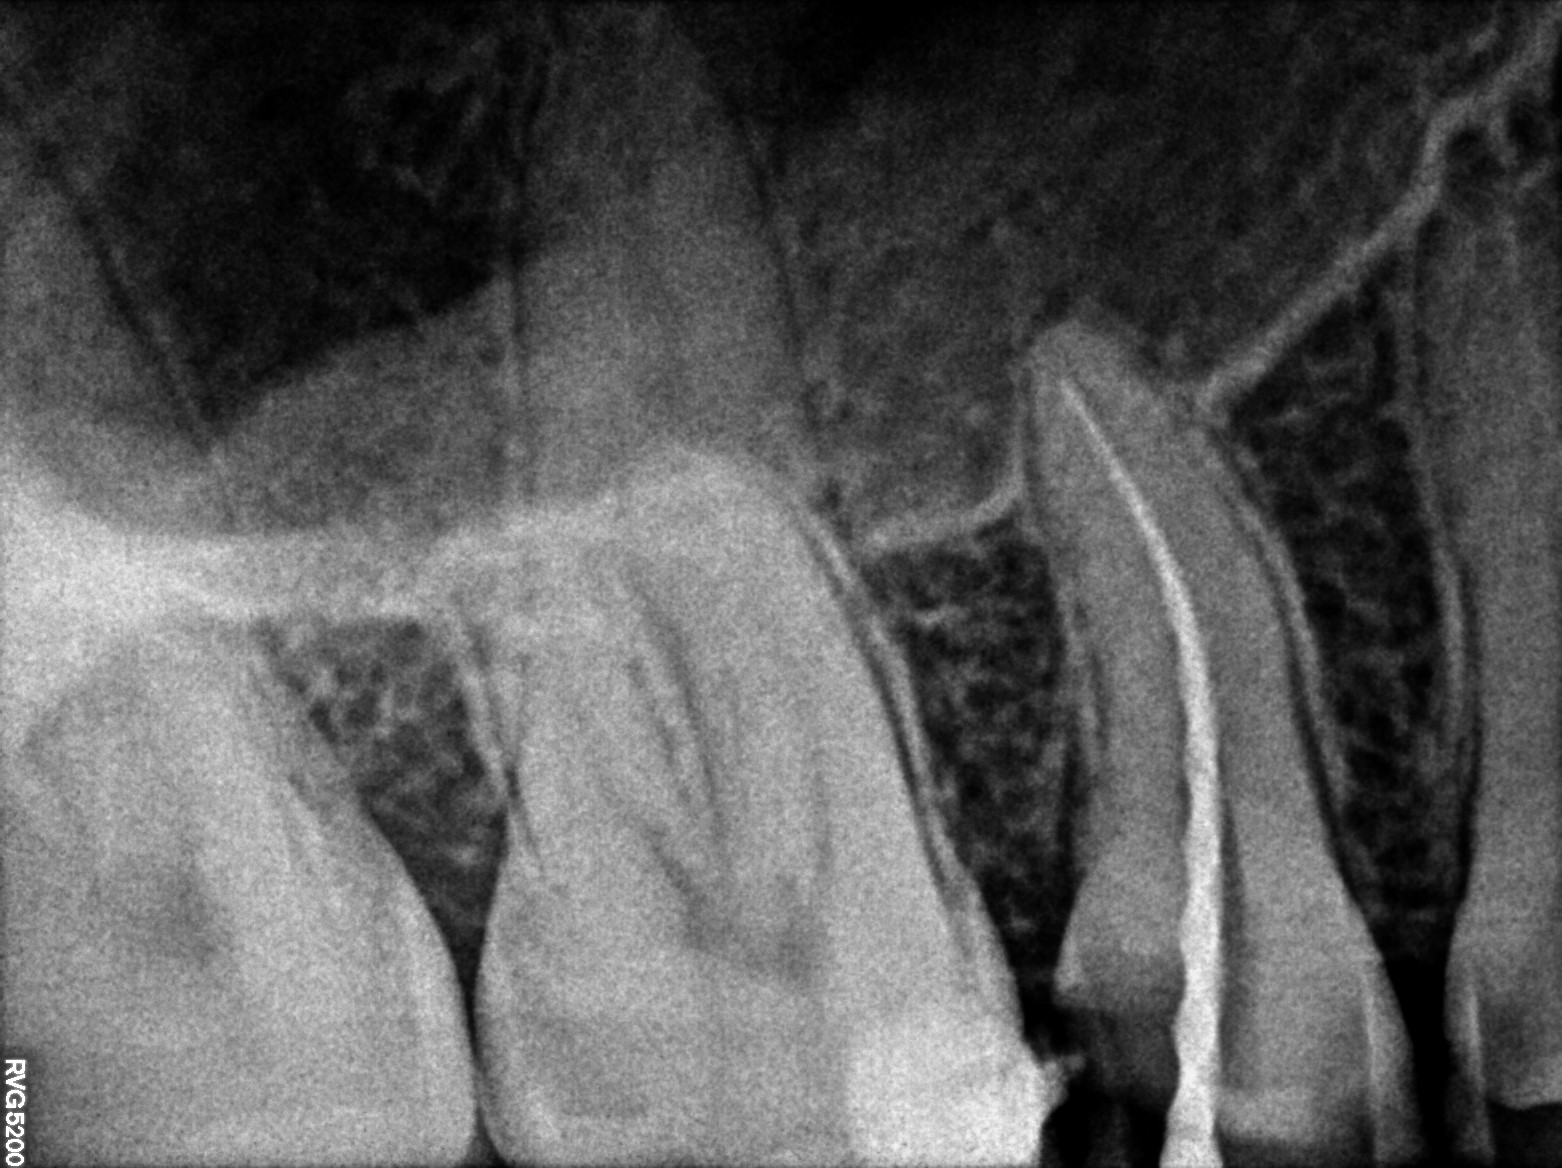

Dental Radiographs FHIR: DocumentReference · LOINC 24641-7

R53.jpg

24641-7